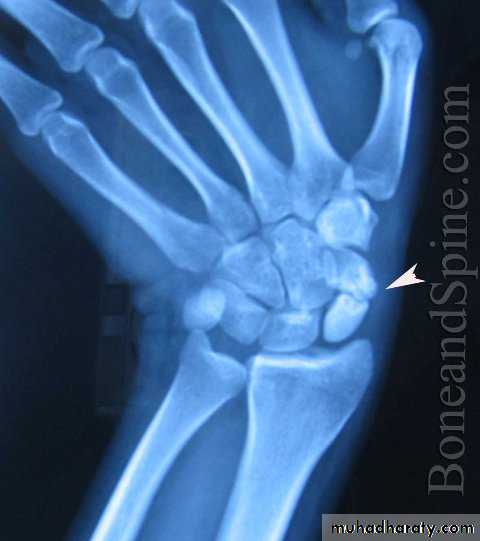

Scaphoid fractures:Its account for almost 75% of all carpal fractures, its rare in the elderly and children.

Mechanism of fracture: fall on dorsiflexed hand.

X-ray : AP, Lateral and oblique views.

Treatment:Undisplaced fracture : casting on glass-holding position for 6 wks.

Displaced fracture: open reduction and internal fixation.

Avascular necrosis: the proximal fragment may die, especially with proximal pole fracture. It appears dense on X-ray after 2-3 months.Non-union: if the fracture is not united after 3 months.